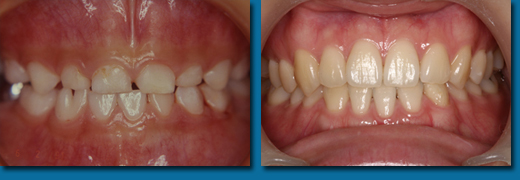

歯並びが悪くなってから治療することを歯列矯正といいますが、乳歯の頃から出てくる歯並びが悪くなる兆候を早期に発見しそれを改善しながらきれいな歯並びの永久歯にしていくことを咬合育成といいます。専門的には歯列矯正と咬合育成は別の物と区別されています。咬合育成は歯並びの予防と考えられ当医院では積極的に取り組み、多くの歯並びの良い子供が育っています。写真の左は乳歯の時、右が永久歯になった時のものです。

咬合育成でおこなうひとつの治療に顎を拡げて永久歯の入るスペースを作るというものがあります。

歯並びの悪い人の多くは顎が小さくて永久歯が並びきらないことが原因になっています。

成長が終わってから矯正治療を受けた方のほとんどが永久歯を4本抜歯してスペースを作って歯並びをきれいにしますが高齢になって歯を失いはじめると最初から歯が4本少ないことは咀嚼をする上でかなりのハンディキャップになります。

なるべく歯を抜かないできれいな歯並びにするには成長期に骨を刺激し、顎を拡げることです。

乳歯から永久歯への生え替わりは6歳くらいから上下の前歯4本から始まり、そして10歳ころから犬歯、奥歯と生え替わり12歳ころで終わります。

はじめに前歯の4本がきれいに並ばなければその後の犬歯、奥歯の生え替わりで歯並びはどんどん悪くなってしまいます。

そのため上下の前歯4本が生え替わる時期に顎を拡げ、きれいに並べておく必要があります。

あまり知られていませんが永久歯の奥歯は乳歯よりも小さいので前歯4本がきれいに並んでいれば奥歯はほとんどがきれいに並びます。

乳歯の時からスペース不足の傾向はでているので個人差はありますが5歳くらいからなるべく早く開始すると安心です。

遅くても8歳になる前には始めなければこの治療法は選択できません。